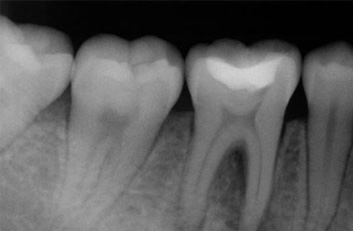

Una endodoncia es un tratamiento que se realiza como última recurso antes de realizar la extracción de una pieza dental. Cuando la caries es muy profunda puede tocar tejidos dentarios llegando al nivel del nervio “pulpa”, esto sucede cuando una caries no fue tratada a tiempo y se perciben molestias al tomar alimentos fríos o calientes, en cuyo caso lo más probable es que sea esto lo que esté sucediendo, el dolor puede llegar a tornarse insoportable y es eso lo que se pretende evitar con una endodoncia el dolor y la posibilidad de una infección con la consiguiente pérdida de una pieza dental. Una endodoncia no duele, se siente igual que un relleno ordinario. La endodoncia es inevitable si lo que se desea es conservar la pieza dental, sin tratamiento, el tejido que rodea el diente se infectaría, por lo que no se debe empastar con una obturación normal, puesto que si lo hacemos, la pieza seguiría molestando, la sensibilidad seria mayor, la infección se diseminará a través del sistema de conductos radiculares del diente produciendo un absceso e irremediablemente la pieza tendría que ser extraída.

Durante un procedimiento de conducto radicular, o endodoncia el nervio y la pulpa se eliminan y el interior del diente se limpia, se empasta la raíz con los materiales correspondientes y se procede a la reconstrucción de la corona dental, todo éste tratamiento se realiza habiendo aplicado anestesia local en la zona afectada, la misma anestesia que se utiliza para un simple empaste o una extracción.